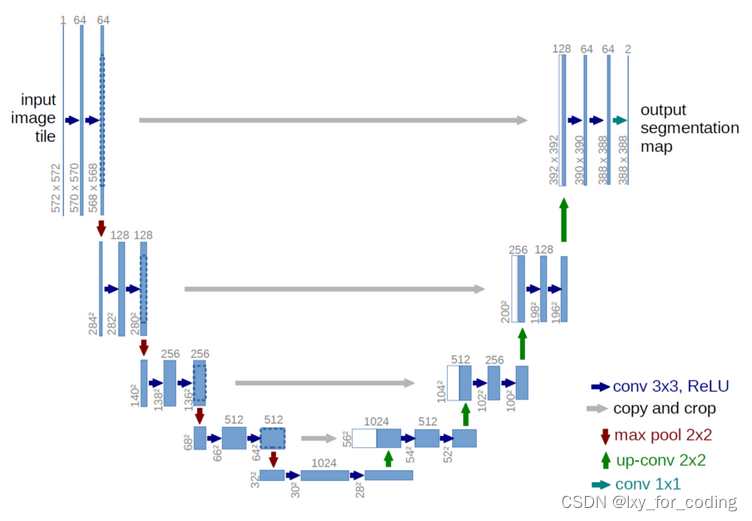

3 U-net 概述

在生物医学图像分析中,语义分割扮演着重要角色,应用广泛,涵盖了 x 射线、MRI 扫描、数字病理、显微镜、内窥镜等领域。更多关于 U-net 的详细讲解,请查看 U-net详细讲解。

step3 U-net模型构建

在我们探索这个 U-net 细胞分割项目的过程中,我们深入了解了在生物医学图像分析领域中的重要应用。通过这个项目,我们更加理解了 U-net 这一强大的语义分割方法,它能够精确地提取细胞图像中的像素点,为生物医学领域的研究和诊断提供了重要支持。

在本文中,我们首先介绍了实验的目的以及所用的数据集、必要的 Python 库和技术。接下来,我们详细解释了 U-net 的工作原理,并探讨了它在生物医学图像分割中的广泛应用。通过深入挖掘相关资源,我们更深入地了解了 U-net 在生物医学领域的多种应用场景和挑战。